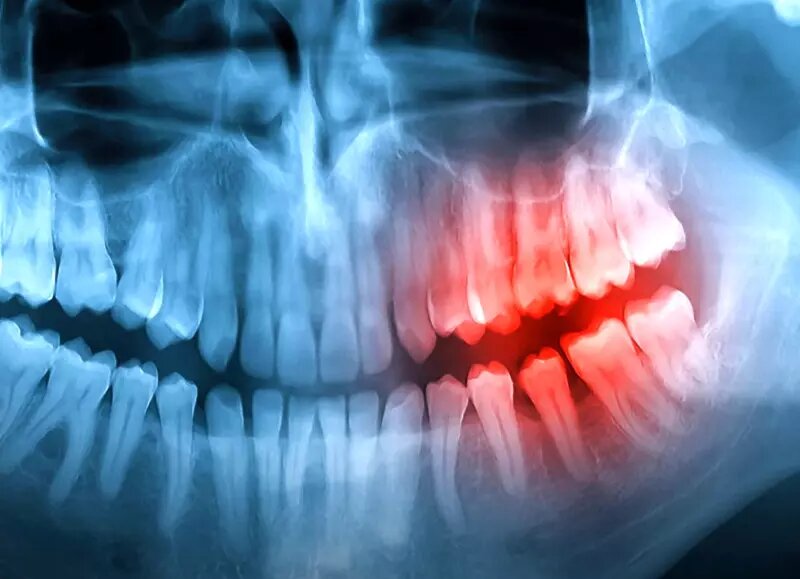

Рентгеновский снимок челюсти человека. Фото: СоцСети.